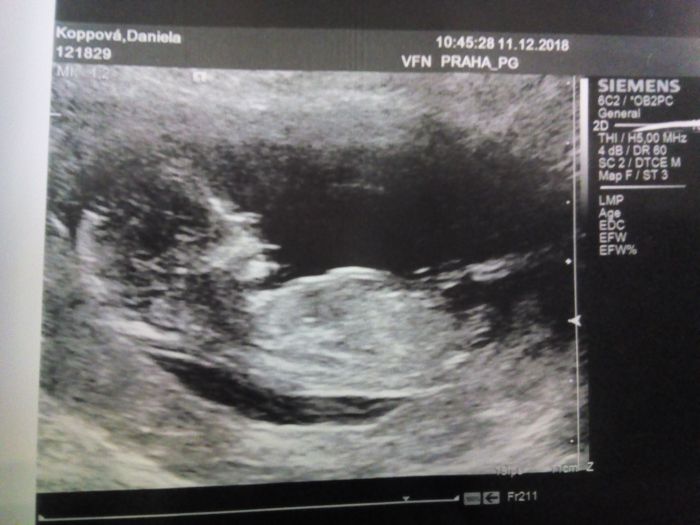

Autor: Daniela 11.12.2018 v 12:59

Ahoj holky, tak jsme taky po screeningu a vše je jak má byt. Jsme moc šťastní ??, dokonce z 12+3 dorostlo na 14+6. Takže se nám tp změnil na 12.6. ?.